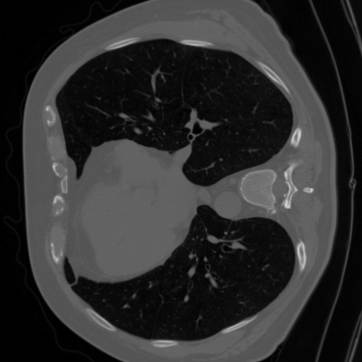

4.2 Forward and Noise Models

We consider two (inverse) problems: denoising and CTreconstruction. The latter has become one of the most accessible imaging modalities in non-destructive testing, security, and medicine. For denoising, it holds that 𝐇=𝐈\mathbf{H}=\mathbf{I}. Additionally, the images 𝐱[0,1]d\mathbf{x}\in[0,1]^{d} are corrupted by additive Gaussian noise 𝐧\mathbf{n} with standard deviation σ=0.1\sigma=0.1. Regarding our CTreconstruction experiment, recall that a scanner acquires multiple measurements while rotating around an object. We model a sparse-view setting, where 𝐇\mathbf{H} is given by the discretized X-ray transform with 60 equispaced angles and a parallel beam geometry. We use the DeepInverse implementation. To keep the setup simple, we consider Gaussian noise with σ=0.7\sigma=0.7 instead of more realistic Poisson noise. For our ground truth images 𝐱[0,1]d\mathbf{x}\in[0,1]^{d}, the measurement range is between 0 and 400. In both settings, we use the data-fidelity D(𝐇𝐱,𝐲)=12𝐇𝐱𝐲2D(\mathbf{H}\mathbf{x},\mathbf{y})=\frac{1}{2}\|\mathbf{H}\mathbf{x}-\mathbf{y}\|^{2}. For CTreconstruction, taking the pseudo-inverse 𝐇\mathbf{H}^{\dagger} is also known as filtered backprojection (FBP).

For the CTreconstruction experiments, we consider the LoDoPaB-CT dataset [89]. Its ground truth images of size 362×362362\times 362 are based on reconstructions in the LIDC/IDRI database [13]. While the original dataset is very large, we use the 35223522 images from the validation set for training, and the 128128 images from the first test batch for testing.